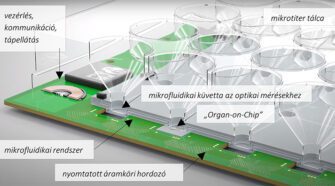

Gyógyszerhatóanyag-vizsgálatok felgyorsítása

Egy új technológia elősegíti a mikrofluidikai Organ-on-Chip rendszerekben kialakított sejtkultúrák kémiai környezetének és metabolizmusának közvetlen feltérképezését és ezen keresztül a betegségek mechanizmusainak és kezelésének megértését. A HUN-REN Energiatudományi Kutatóközpont Műszaki Fizikai és Anyagtudományi Intézetének (HUN-REN EK MFA) kutatói az Aedus Space Kft.-vel és a holland Micronit B.V. céggel együttműködve mikroszkopikus környezetben alkalmazható optikai és elektrokémiai …